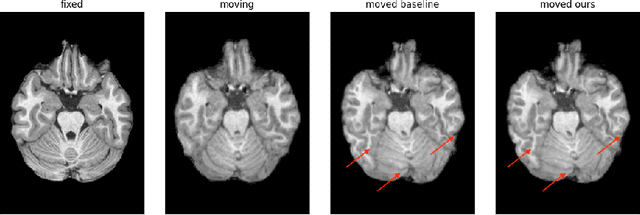

Abstract:Unsupervised deep learning is a promising method in brain MRI registration to reduce the reliance on anatomical labels, while still achieving anatomically accurate transformations. For the Learn2Reg2024 LUMIR challenge, we propose fine-tuning of the pre-trained TransMorph model to improve the convergence stability as well as the deformation smoothness. The former is achieved through the FAdam optimizer, and consistency in structural changes is incorporated through the addition of gradient correlation in the similarity measure, improving anatomical alignment. The results show slight improvements in the Dice and HdDist95 scores, and a notable reduction in the NDV compared to the baseline TransMorph model. These are also confirmed by inspecting the boundaries of the tissue. Our proposed method highlights the effectiveness of including Gradient Correlation to achieve smoother and structurally consistent deformations for interpatient brain MRI registration.